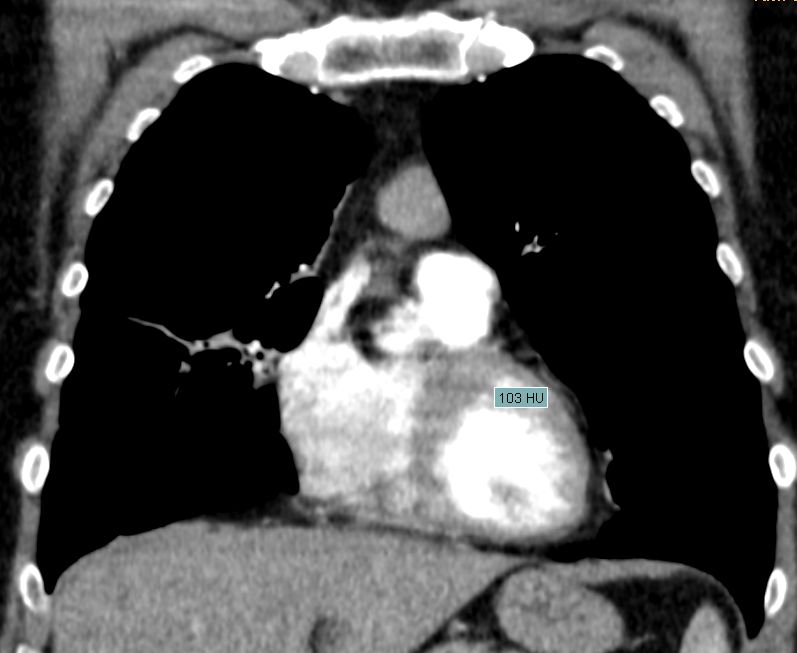

Diagnostik B3-Thymom mit Infiltration des Fettgewebes.